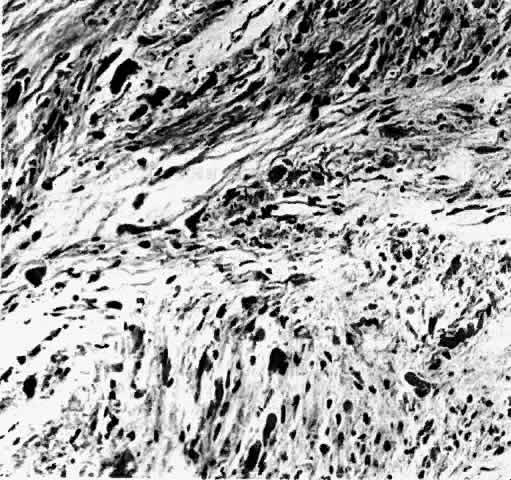

Gross examination of optic nerve gliomas usually reveals a smooth, fusiform, intradural

enlargement of the optic nerve (Fig. 6). After extending through the optic canal in a dumbbell fashion, there

may be extension to posterior structures.4 Most optic gliomas are classified as juvenile pilocytic astrocytomas and

have a benign histologic appearance. Pilocytic refers to the spindle-shaped astrocytes with elongated nuclei that are

often arranged in a parallel fashion (Fig. 7). Oligodendroglial cells may be scattered throughout the glioma. These

tumors can contain carrot- or cigar-shaped eosinophilic astrocytic cytoplasmic

inclusions known as Rosenthal fibers4 (Fig. 8). Microcystoid extracellular spaces containing acid mucopolysaccharide

generated by mucin-producing astrocytes are often seen.85 Less common features can include capillary hyperplasia, mitotic figures, tissue

necrosis with hemorrhage,86 and glial giant cells.4